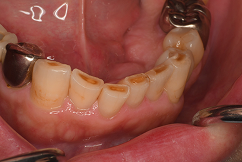

症例紹介②

| 患者さまのお悩み | |

|---|---|

| 治療内容 | |

| 年齡 | |

| 性別 | |

| 治療期間 | |

| 治療費 | |

| 治療で得られるメリット | |

| 治療する際に起こる リスク・副作用 |